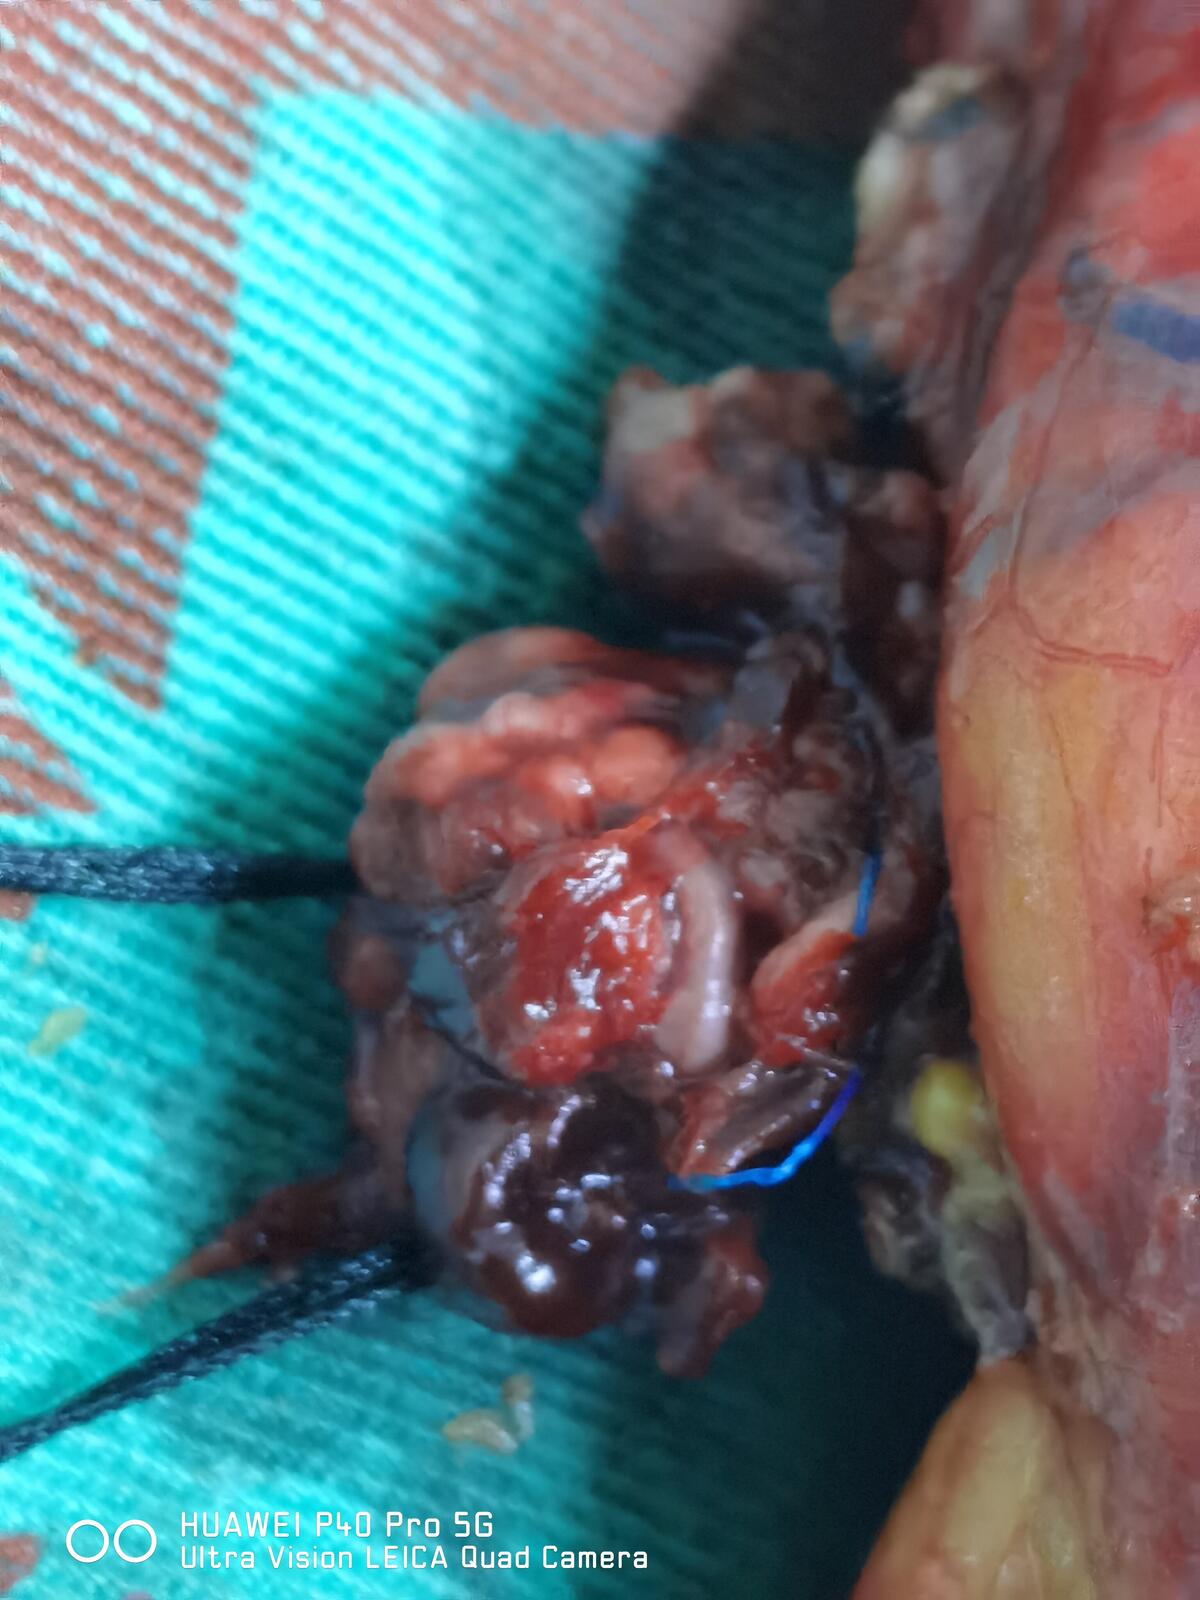

采用静吸复合全身麻醉,取健侧斜卧70°,腰部抬高,留置16F双腔导尿管。在右侧腹直肌外侧缘脐上2cm处做1.5cm皮肤切口,建立气腹,置入12mm套管,直视下分别于右侧锁骨中线肋缘下1cm、右侧髂前上棘上方2cm处做1cm切口,置入1、2号机械臂8mm套管,再分别于前正中线脐上3cm、8cm及经右侧腹直肌脐下5cm做1.2cm切口,置入第1、2、3辅助孔套管,装配机械臂,扇形拉钩挡开肝脏,电剪刀分离并打开右侧结肠旁沟及结肠脾区,将升结肠及十二指肠翻至左侧,暴露右肾周筋膜,打开下腔静脉鞘,沿下腔静脉表面充分游离,见右侧生殖静脉明显增粗、僵硬,并在生殖静脉与下腔静脉之间见一异位肾动脉穿行。向上游离至肝短静脉水平,并夹闭离断,向左充分游离左肾静脉,在腔静脉与腹主动脉之间显露左肾动脉并夹闭。于下腔静脉表面用Hem-o-lok夹闭并离断右侧生殖静脉。充分游离并夹闭离断下腔静脉深面腰静脉。充分游离肾脏并切除肾上腺,分离肾蒂血管周围组织,显露右肾静脉。使用血管吊带于癌栓头侧及尾侧环套下腔静脉,同样方法环套左右肾静脉。提拉血管吊带并以Hem-o-lok固定依次阻断癌栓尾侧下腔静脉、左肾静脉、癌栓头侧下腔静脉。于右肾静脉根部纵行切开下腔静脉5cm,完整取出下腔静脉内癌栓并切除部分与之粘连的右侧下腔静脉壁,并连同右肾完整切除,5-0CV线连续缝合关闭下腔静脉切口,开放左肾静脉排出下腔静脉内气体后缝线打结,完全关闭下腔静脉,并检查下腔静脉有无漏口,依次松开远心端及近心端血管吊带。彻底止血,取出标本,放置引流后逐层关闭切口。

术中穿刺套管的布局以更好地显露下腔静脉为原则,并适当增加床旁助手的操作通道。术中操作以游离下腔静脉为中心,不急于处理肾蒂血管。在头侧,分离并离断肾上腺中央静脉及肝短静脉,尽量增加癌栓上方可利用腔静脉长度;在尾侧本例手术中发现伴有癌栓的生殖静脉从腔静脉表面汇入,并在两者之间有异位肾动脉穿过;游离腔静脉左侧时应注意保护左肾静脉。离断术区所有腰静脉是避免腔静脉阻断切开取栓时大量出血的关键步骤。夹闭右肾动脉,并将腔静脉、左肾静脉、右肾静脉充分游离后,以血管阻断带阻断癌栓两端腔静脉及左肾静脉,切开取栓时应注意癌栓的性状、是否侵犯腔静脉壁等,我们建议腔静脉管腔可保留40%以上时无需用人造血管补片修补。